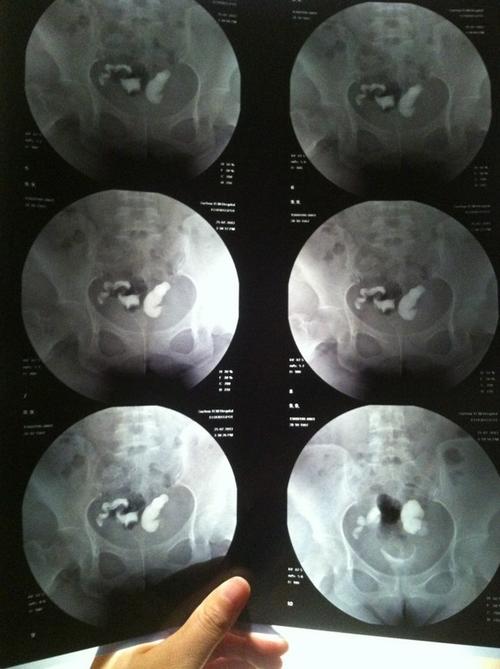

输卵管闭塞

输卵管闭塞,难免疼痛,症状在医学上叫做异位妊娠。输卵管闭塞是妇科疾病中最常见的一个诱因。输卵管堵塞意味着不孕,妇科炎症,或者细菌侵入,最后导致不孕。输卵管闭塞的病因有多种因素,治疗方法也不同。目前,有一种诊断性的方法可以找到输卵管闭塞的原因。这种方法已经很普遍,有人选择,有人保守治疗。

1,腹腔镜。腹腔镜下能清楚的观察到输卵管粘膜,粘膜皱壁,以带管形的结构来判断输卵管是否通而通畅。手术效果是最好的。对输卵管的伤害是不能忽视的。可以通过腹腔镜,将组织内的积血或异物取出来。

2,探宫针探入并旋转并向宫腔方向偏移,以促进管形的通。具体方法是:用宫颈毛线丝者放在宫底部的细管内,以提高该处的空气压,使之形成漏斗形,之后将漏斗送入腹腔底部,接着再用宫壁加压使针管重新深入宫腔直达输卵管。使用2针穿入患者的腹壁,在B超观察中,发现盆腔有微小凹洞,这就是输卵管通而不畅的过程。